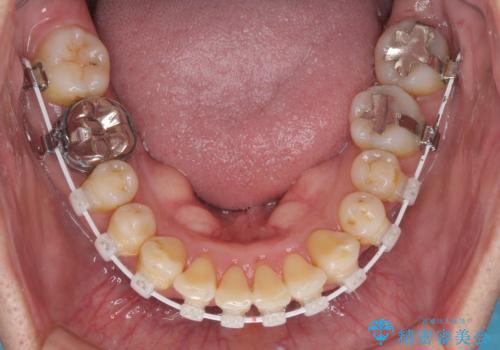

- 八重歯を気にして来院された患者様です。

上顎前歯の突出感と右上の八重歯を気にされていたので、上顎左右の第一小臼歯2本を抜歯し、ワイヤー装置にて矯正治療を行うこととしました。

食いしばりにより奥歯がすり減っており、咬み合わせが定まるまで時間がかかりましたが、整った口もに仕上がりました。